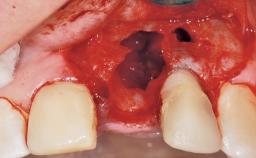

Immediate Placement of an Implant in a Maxillary Left Central Incisor Site

A 33-year-old female patient presented with an upper left central incisor that required extraction after a failed endodontic therapy. The tooth had been traumatized when the patient was a teenager and had undergone several endodontic treatments, including two apicectomy procedures. The patient was in good health and did not smoke. Clinical examination showed that the patient had a high lip line. In full smile, the gingival margins of the upper teeth were visible to the first molars. The gingival margins of central incisors 11 and 21 were only just showing. Examination of tooth 21 confirmed that the tooth was mobile and had hypererupted by 1 mm.

| Placement Protocol | Immediate implant placement |

| Tooth Site | Maxillary incisor or canine |

| Socket Morphology | Single-root socket |

| Socket Integrity | Damage to one or more bone walls |

| Bone Volume | Damage to one or more socket walls |